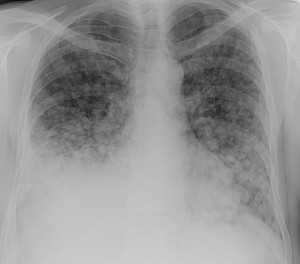

Гематогенные метастазы саркомы мягких тканей бедра на КТ (справа) и рентгенограмме (слева).

Обратите внимание на увеличение и нарушение структуры корня правого легкого. Это центральный рак. Кроме того, выявлены очаговые тени в обоих легочных полях (гематогенное распространение), а также «лучи», идущие радиально от опухоли корня (лимфогенное распространение).